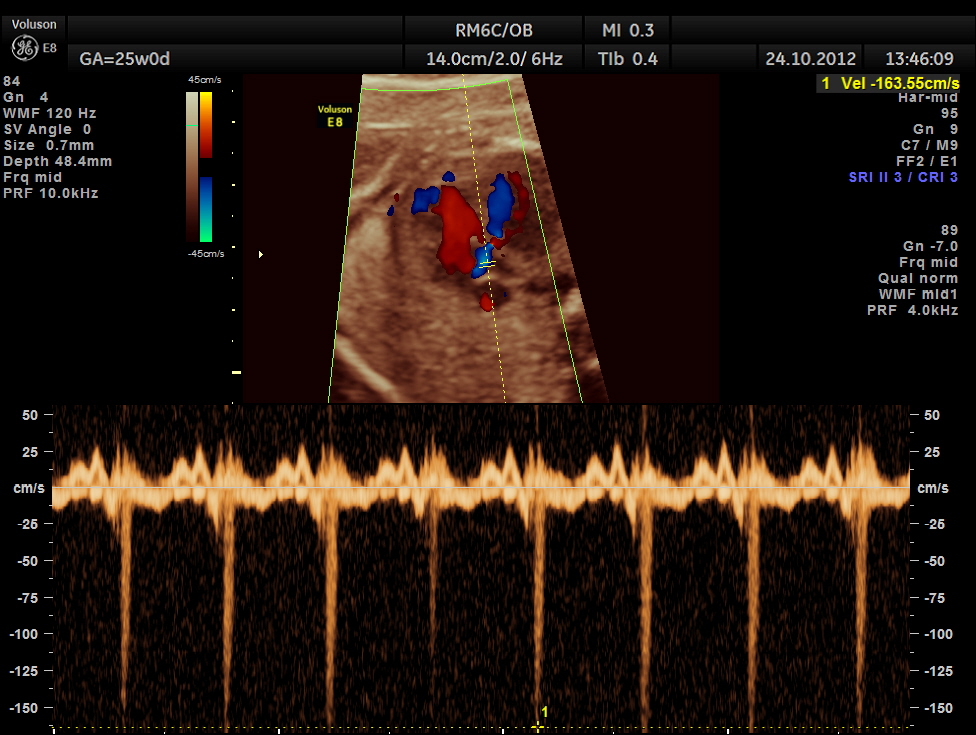

Spectral doppler shows high velocity flow across the defect